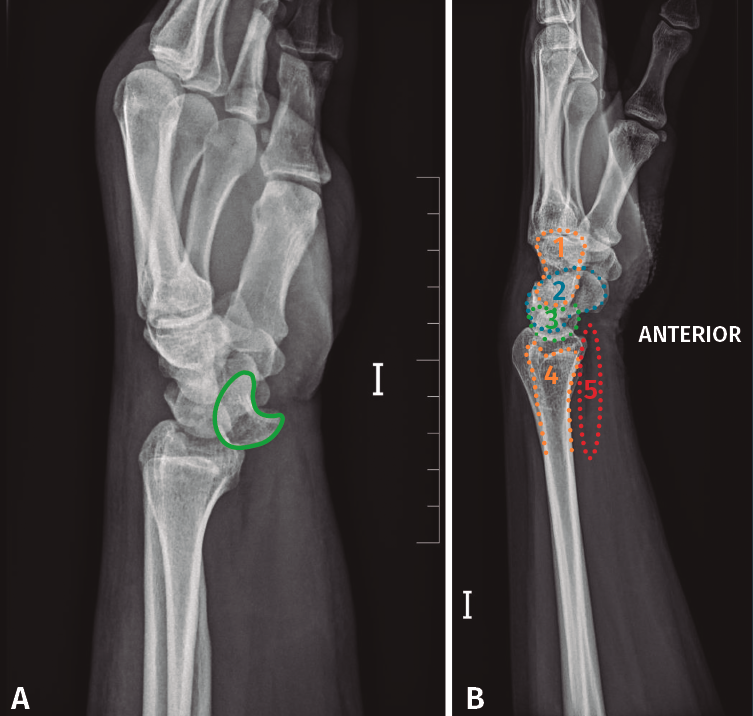

• Qué ver en una radiografía lateral de muñeca (Figuras 5A y 5B). Para valorar que estamos ante una correcta proyección, debemos obtener:

– Obtener vista lateral de la región media de los metacarpianos, del carpo, de la articulación radio-cubital distal.

– La cabeza del cúbito debe estar superpuesta sobre el radio distal.

– Las regiones proximales de los metacarpianos 2.º-5.º están alineadas y superpuestas.

Figura 5. A: radiografía lateral de luxación transestiloperilunar; B: radiografía lateral sin alteraciones. Recuerdo anatómico. 1: grande; 2: escafoides; 3: semilunar; 4: cúbito; 5: almohadilla grasa pronadora.

En la radiografía podemos observar los siguiente ítems:

– Debemos prestar especial atención a la congruencia radio-semiulnar-hueso grande. Normalmente los 3 huesos deben formar 3 C alineadas.

– Valorar que no existan interrupciones en las corticales de los huesos.

– Fracturas y luxaciones de radio. Valorar la inclinación dorsal o palmar.